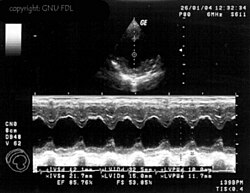

Eine weitere häufig eingesetzte Darstellungsform ist der M- oder TM-Mode (englisch für (time) motion). Dabei wird ein Strahl bei einer hohen Impulswiederholungsfrequenz (1 – 5 kHz) eingesetzt. Die Amplitude des Signals wird auf der vertikalen Achse dargestellt; die von den hintereinander liegenden Impulsen erzeugten Echozüge sind auf der horizontalen Achse gegeneinander verschoben. Diese Achse stellt also die Zeitachse dar.

Bewegungen des Gewebes bzw. der untersuchten Strukturen haben Unterschiede in den einzelnen Impulsechos zur Folge, es lassen sich Bewegungsabläufe von Organen eindimensional darstellen. Die M-Mode-Darstellung ist häufig mit dem B- bzw. 2D-Mode gekoppelt.

Ihre Hauptanwendung findet diese Untersuchungsmethode in der Echokardiografie, um Bewegungen einzelner Herzmuskelbereiche und der Herzklappen genauer untersuchen zu können. Die zeitliche Auflösung dieses Modus ist bestimmt durch die maximale Wiederholrate der Schallimpulse und beträgt schon bei 20 cm Tiefe über 3 kHz.

-

Anwendung des Doppler-Verfahrens bei einer Herzuntersuchung: Mitralklappeninsuffizienz -

Gewebe-Doppler im Myokard